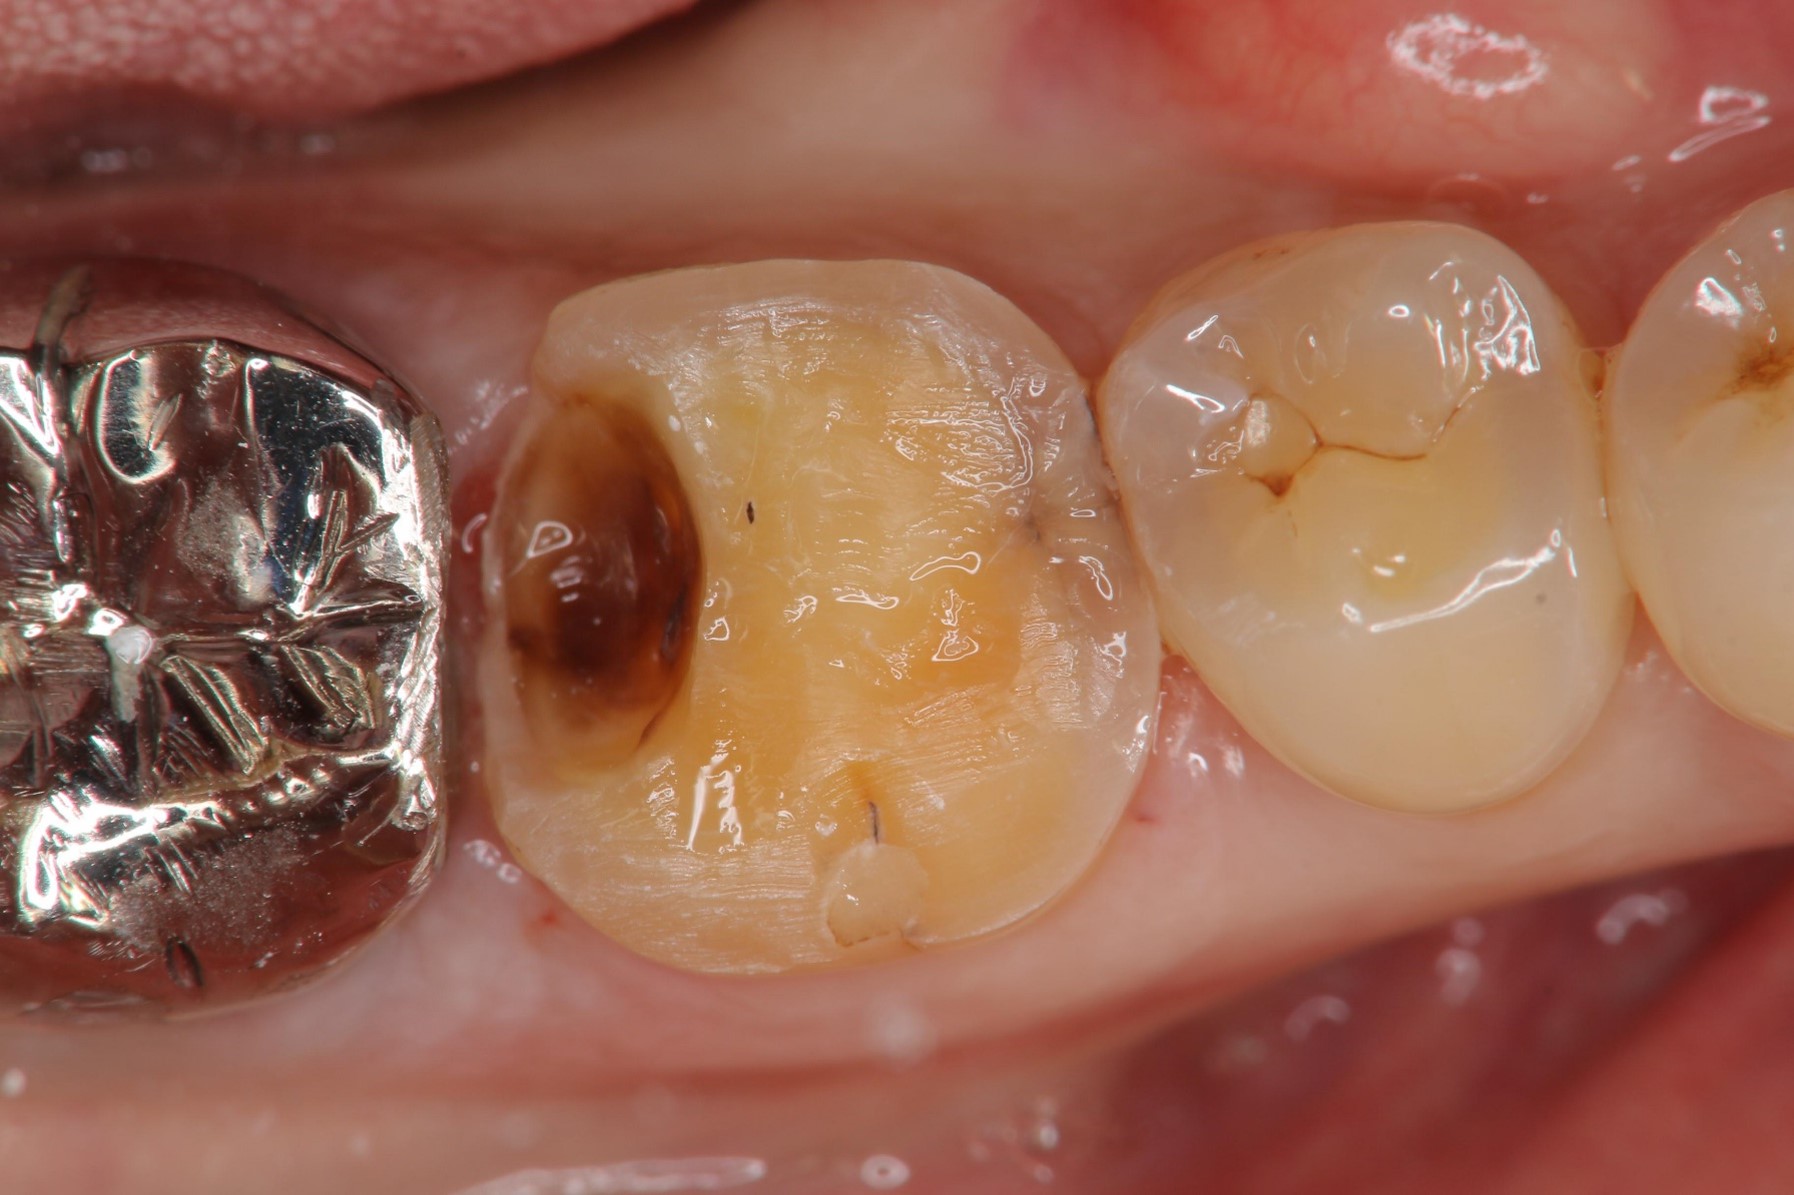

冠塊體體製備

當蛀牙破壞程度大